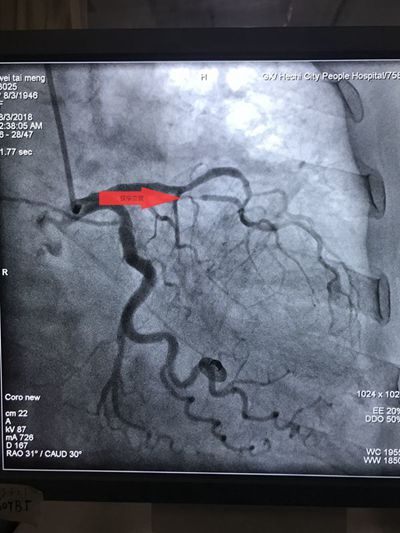

从穿刺、造影、球囊扩张......整个手术医护人员默契配合,两枚救命的支架顺利植入韦婆婆体内,整个过程用时51分钟。术后韦婆婆的胸痛症状立即得到缓解。